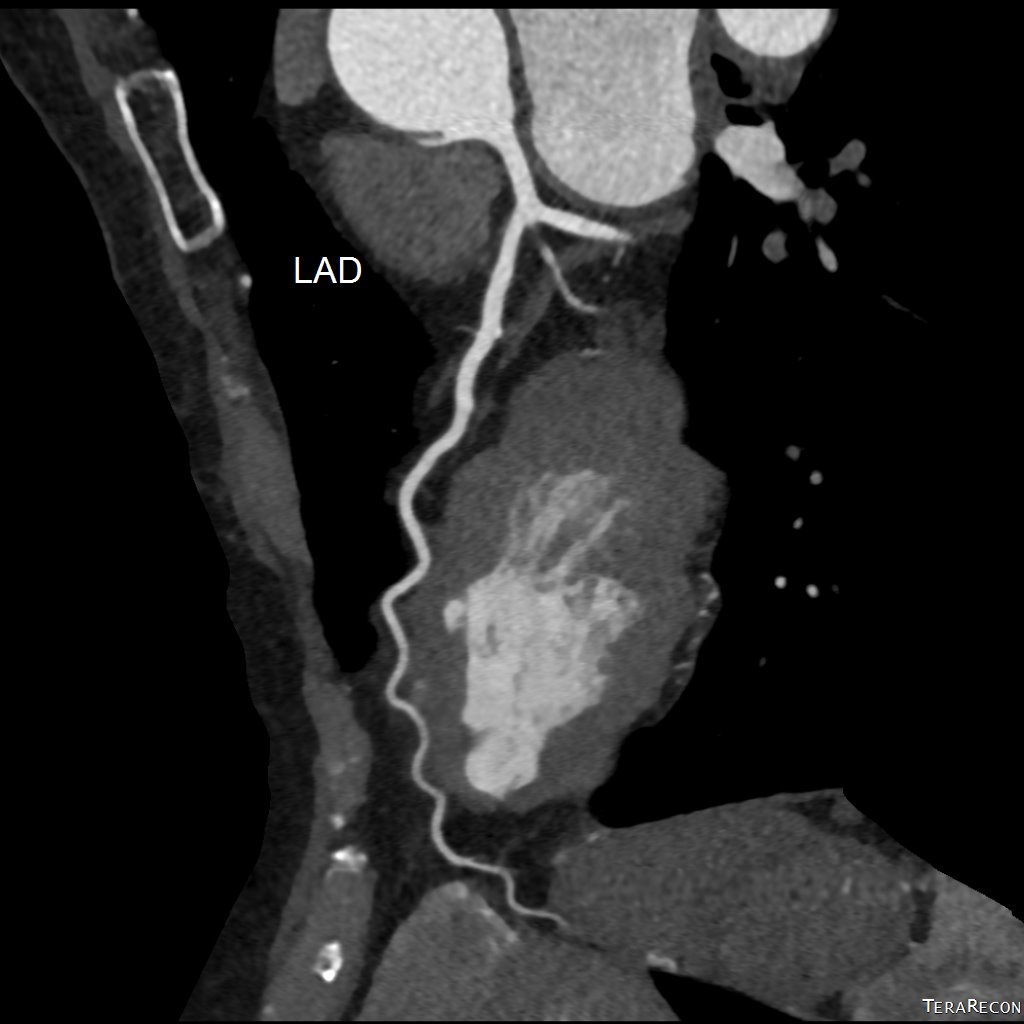

冠狀動脈電腦掃描造影

(CT Coronary Angiogram)

冠狀動脈CT造影 是目前評估心血管疾病風險的重要非入侵性工具,可:

• 清楚顯示冠狀動脈有否出現狹窄、阻塞或鈣化

• 為懷疑有心絞痛或心肌缺血的患者提供早期診斷依據

• 協助心臟科醫生決定是否需進一步介入性治療,如通波仔(PCI)